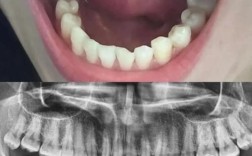

精确评估:

- CBCT: 是诊断骨量不足的金标准,能清晰显示骨的高度、宽度、密度以及与重要解剖结构(如下颌神经管、上颌窦)的关系。

- 临床检查: 检查口腔软组织健康状况、咬合关系、邻牙情况等。